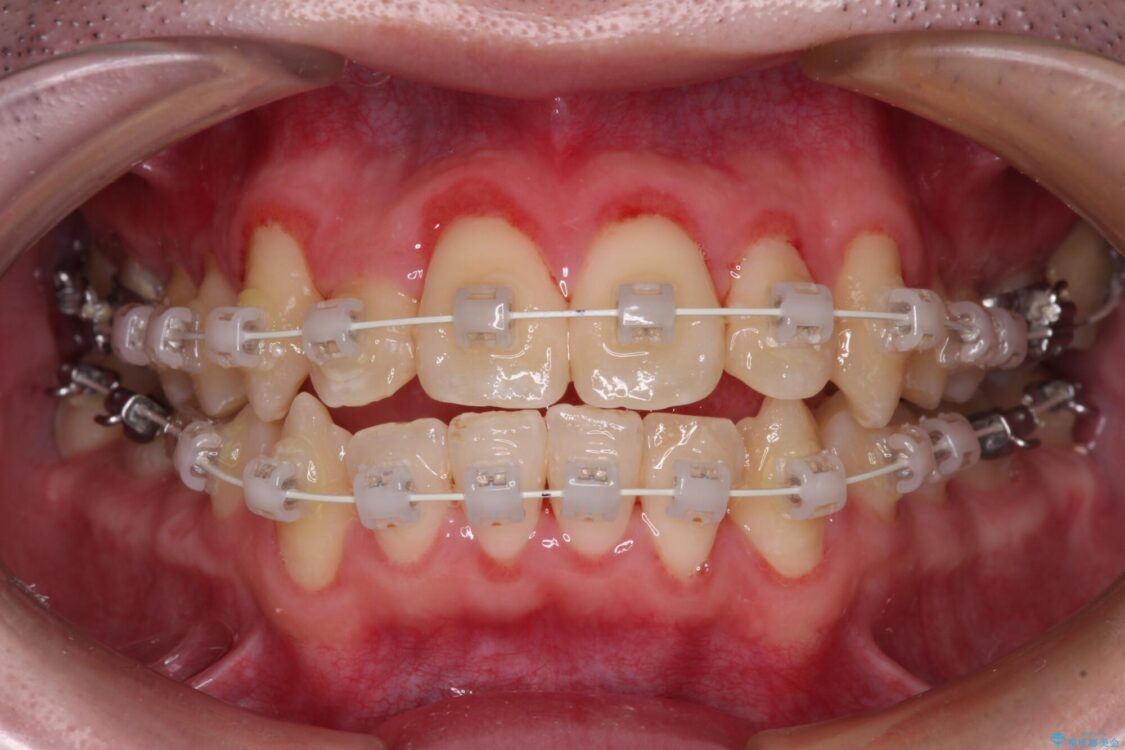

治療途中

• 全顎的なクロスバイト 補助装置を用いてワイヤー矯正 治療途中画像